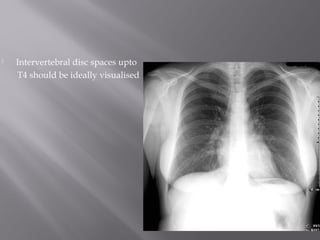

 Intervertebral disc spaces upto

T4 should be ideally visualised

 Intervertebral discspaces upto T4 should be ideally visualised